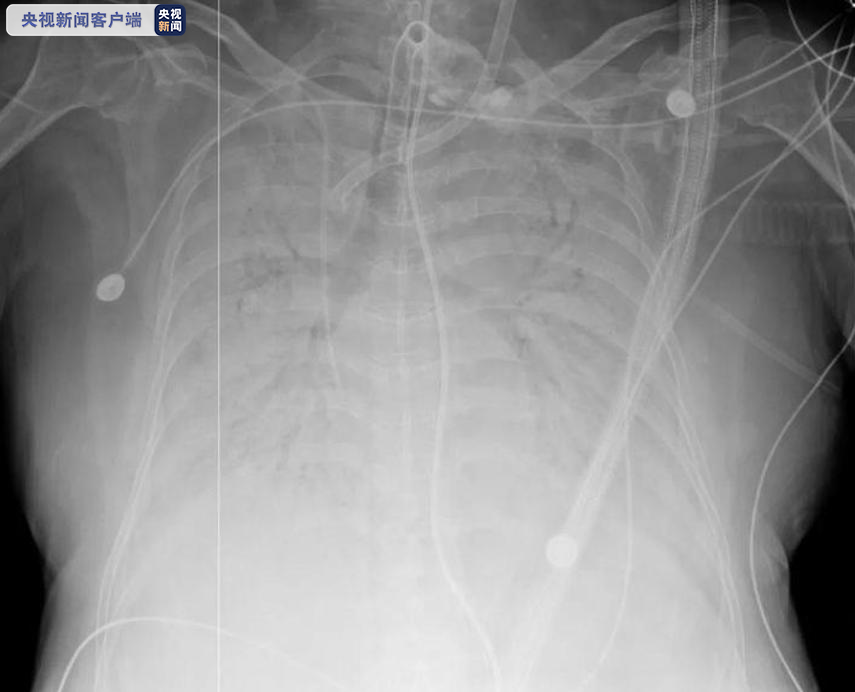

据了解,这位66岁的女性患者1月31日确诊,2月2日从浙江某地转院至浙大一院抢救,病情进展迅速。2月3日和16日先后气管插管和使用上ECMO。经过浙大一院的精心救治,她的病毒核酸检测已经连续多天转阴,但双肺实变严重,肺功能受损不可逆,想要延续生命唯一的方法就是肺移植。

上午10:30,供体捐献完成。13:05,做好全套防护措施,戴上正压头套,肺移植科主任韩威力主刀,ECMO下的肺移植手术正式开始。下午17:00,供肺到达之江院区手术室,医生随即开始修整。晚上21:18,双肺顺利移植完成。